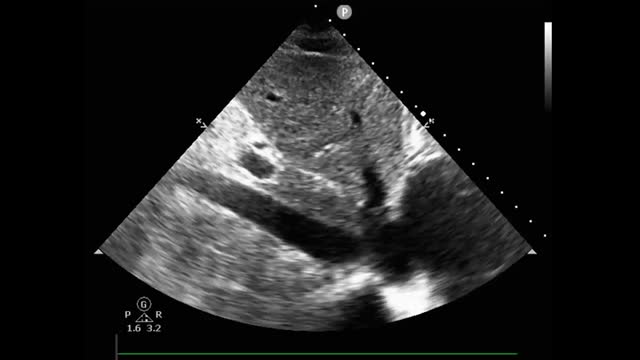

A 35-year-old woman presented to the emergency department with dyspnea and chest tightness lasting for 1 day. Computed tomographic pulmonary angiography confirmed the diagnosis of acute pulmonary embolism (Fig. 1a, yellow arrow). Venovenous extracorporeal membrane oxygenation (VV-ECMO) was implanted due to severe hypoxemia (a P/F ratio of 64 mmHg). Three days later, VV-ECMO was successfully decannulated, and an immediate ultrasound examination detected a rare morphology of ECMO-related thrombus in the inferior vena cava (IVC): a pedunculated, polypoid mobile thrombus floating with a heartbeat (Video 1 and Fig. 1b). The IVC thrombus dissipated after a 3-week standard anticoagulant treatment (Video 2). The case indicated the necessity of routine IVC ultrasound examination after the decannulation of ECMO.